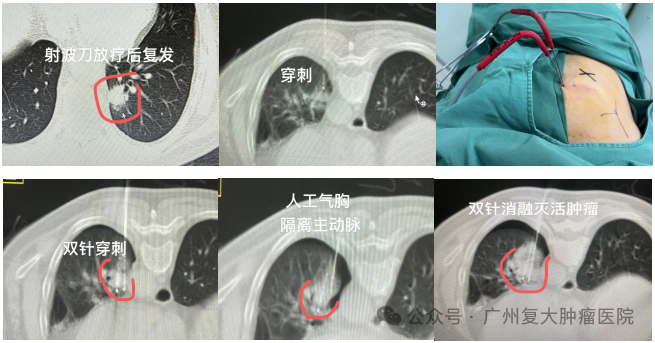

▲一位福建的肺结节患者,五年前行右肺结节切除,后来左肺新长肺结节,接受射频消融后肺结节反而增大并紧靠主动脉。近日复大医院在人工气胸辅助下顺利为其完成肺结节冷冻消融术。